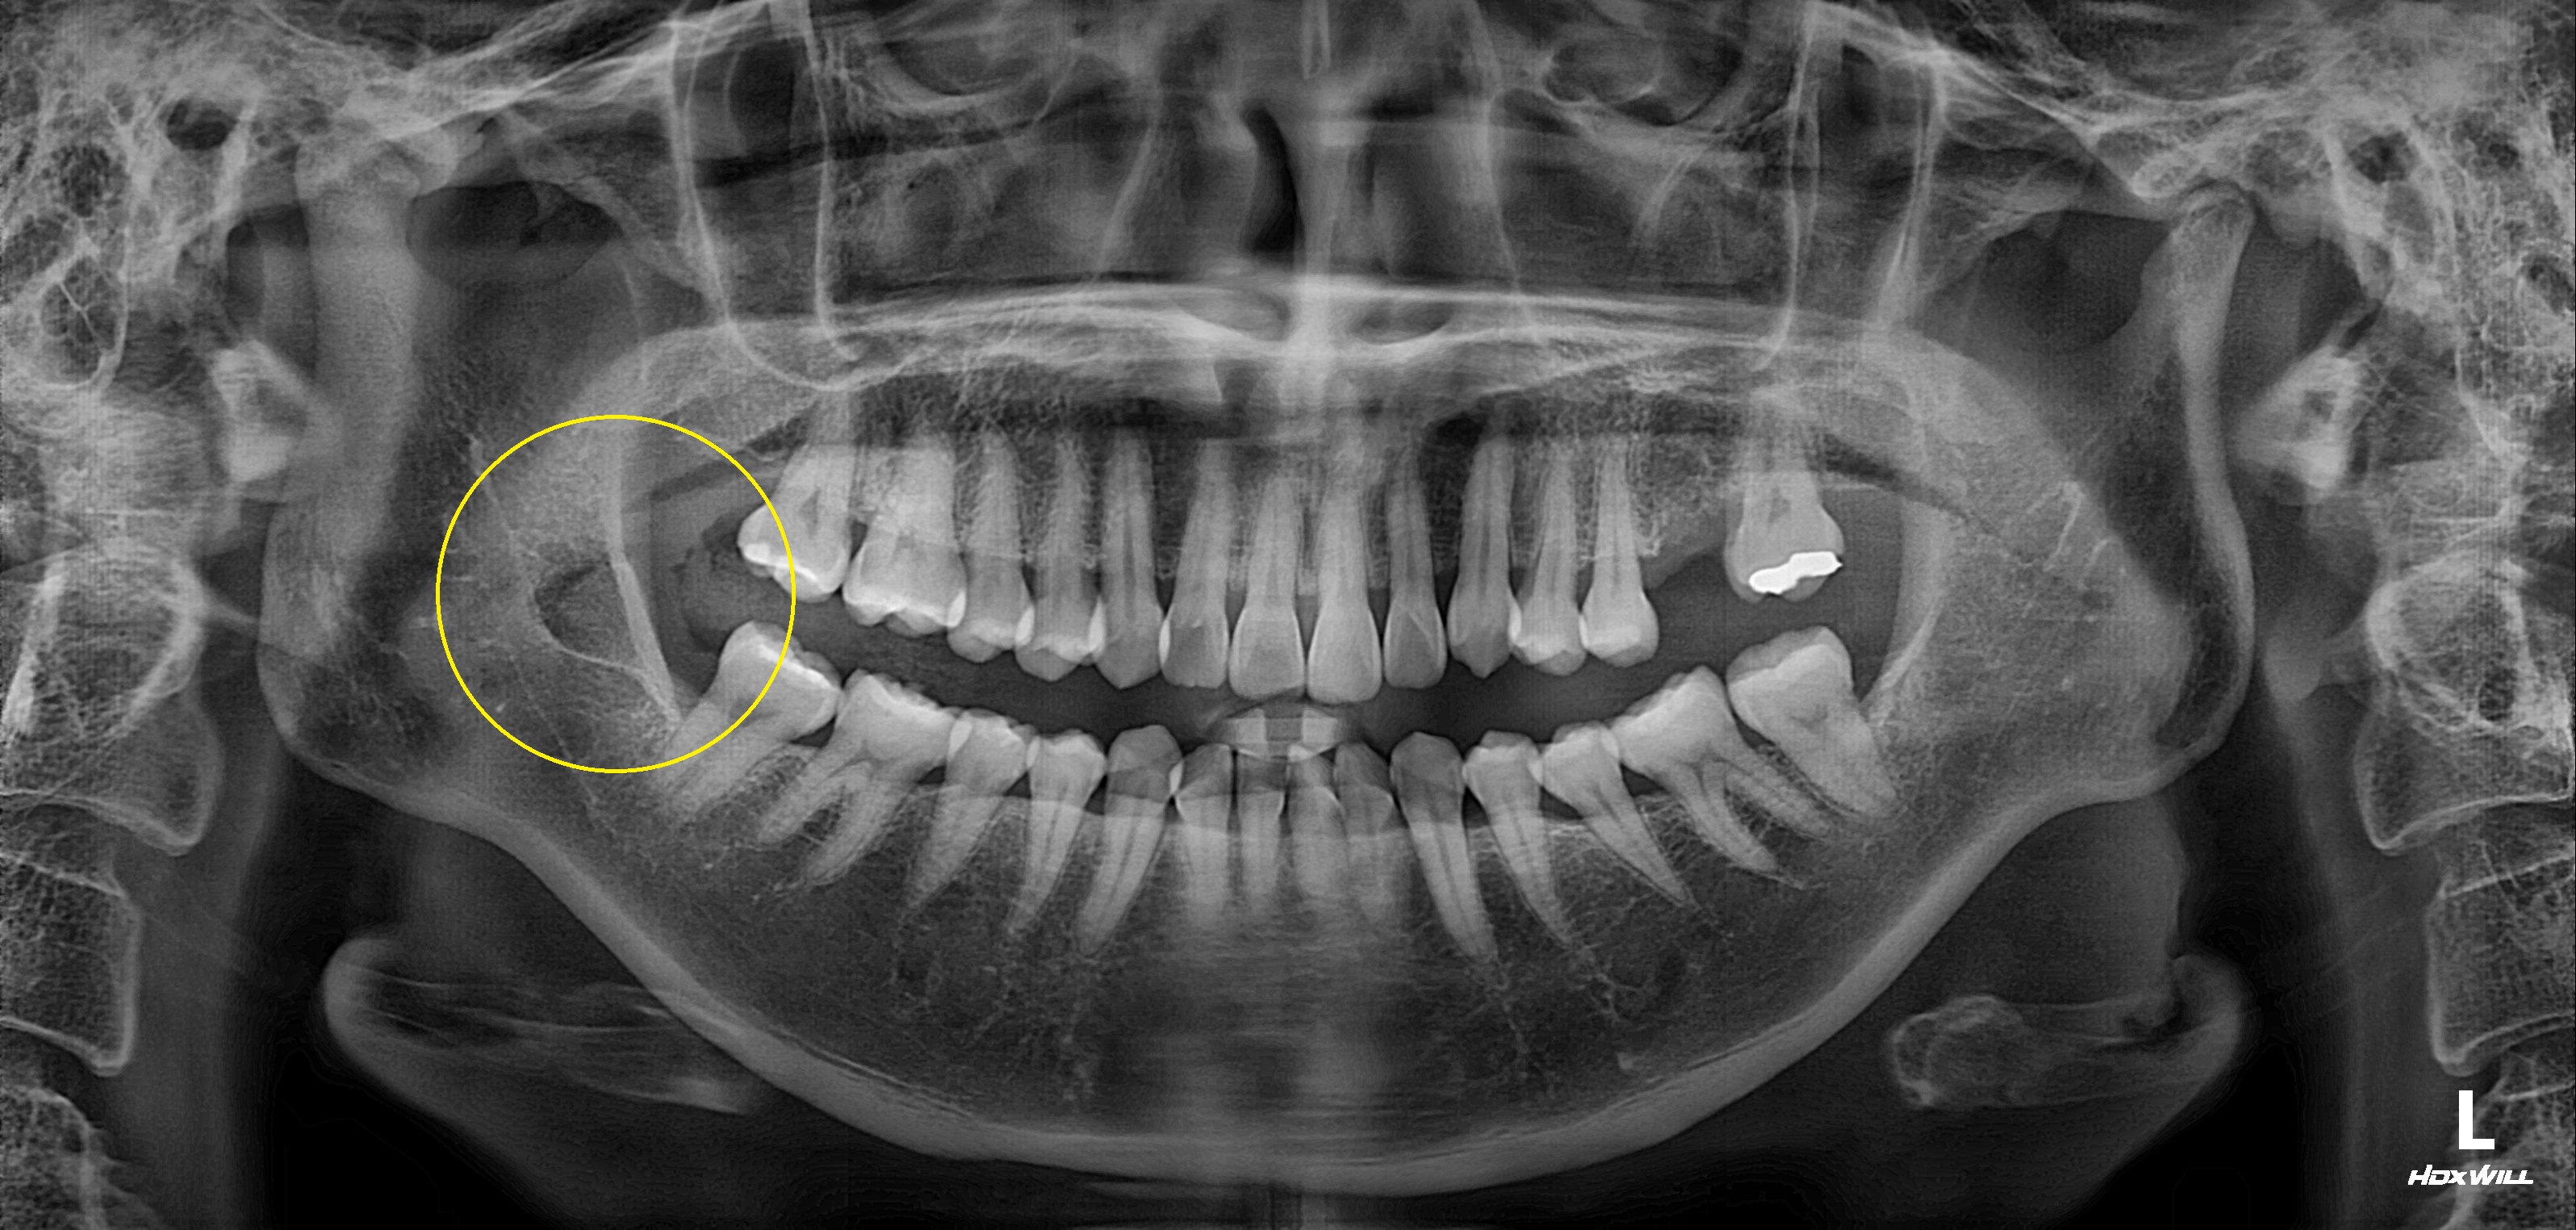

수술 전

수술 후

완전매복치발치사례

전후사진